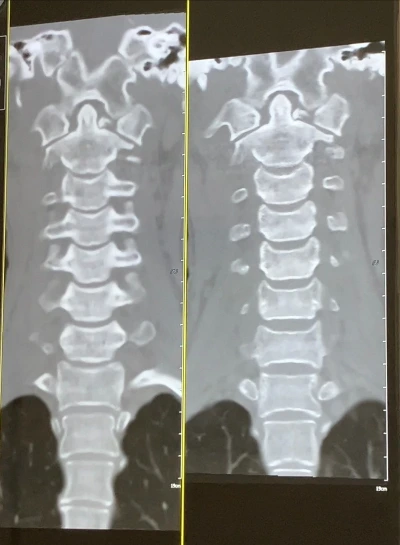

이번이 4번째 ct죠?

같이 사진 한 번 볼게요.

음….

뭐 비슷하네요.

저번달과 비슷해요

붙고는 있어요. 근데 너무… 더뎌.

이게 뼈가 부러질 때 워낙

크게 박살이 난 대다

절단면도 클리어하게 깔끔하지 않고

뼛조각이 날라가 버렸으니

뼈와 뼈 사이의 공간, 갭이

너무 커요. 이게 더딜 수 밖에 없어…”